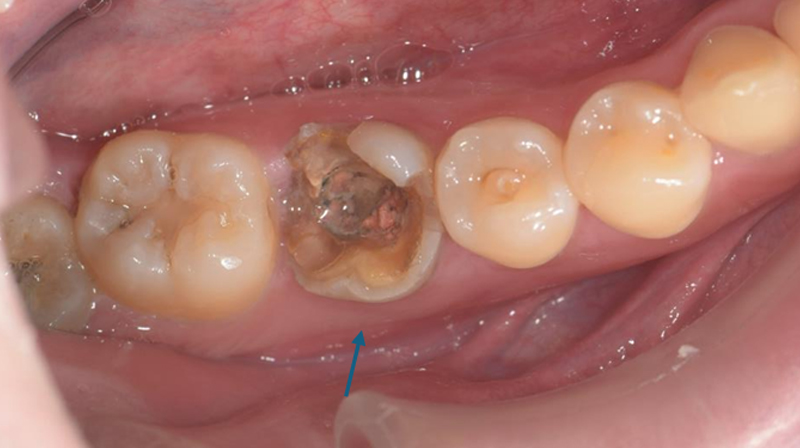

拔除右下第一大臼齒